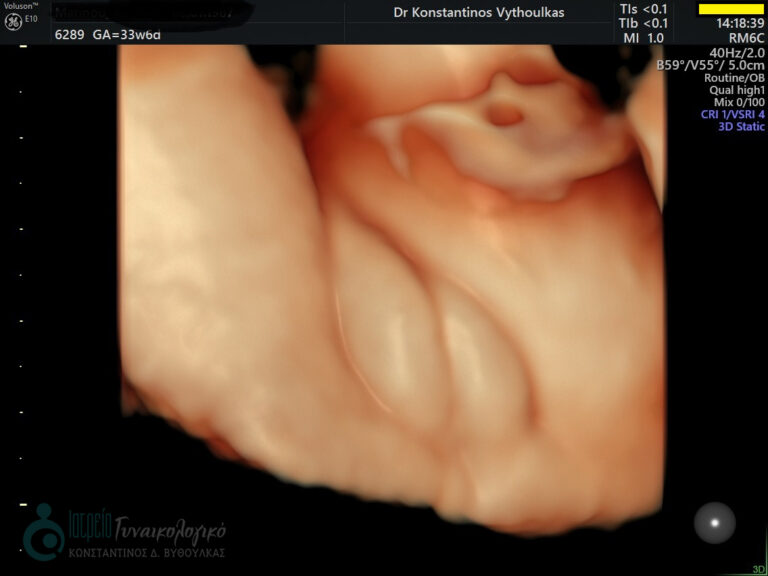

- Υπερηχογραφική εξέταση, η οποία συμβάλλει στη διαπίστωση της ενδομήτριας κύησης και αποκλεισμό της έκτοπης κύησης. Επιπλέον, μπορεί να διαπιστώσει εάν πρόκειται για μονήρη ή πολύδυμη κύηση, να ανιχνεύσει την εμβρυϊκή καρδιακή λειτουργία μετά τις 6 εβδομάδες και να προσδιορίσει υπερηχογραφικά την ηλικία κύησης, με βάση το κεφαλουραίο μήκος του εμβρύου μετά τις 8 εβδομάδες.